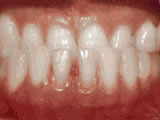

Deep overbite - Lower front teeth bite into palate

This adult patient, age 25, required braces and jaw surgery to correct his severe overbite, with treatment taking two years. His problem could have been corrected without surgery if he had been treated before he was a teenager.